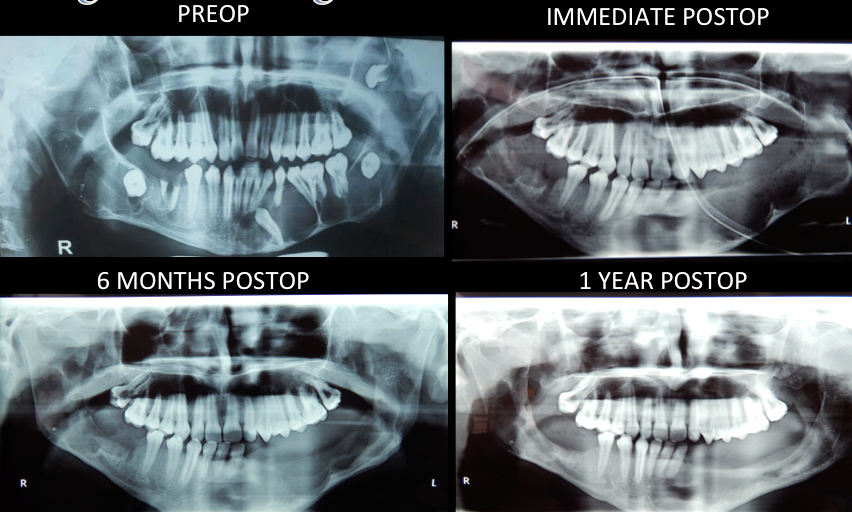

Corrective Jaw Surgery / Orthognathic Surgery

Corrective jaw surgery is aimed at correcting the dentofacial disharmonies through combination of surgery of upper and lower jaws and orthodontics.

Basic goals of this surgery are to provide normal mastication, Speech, Oral function and respiratory function, facial harmony and balance.

After growth completion this surgery can be accomplished at any time presurgical and postsurgical orthodontics are part of complete treatment. Surgery is performed under general anaethesia with all the preoperative evaluations and pictures.

Recovery period is usually smooth and safe, although there can be some complications as is with any other surgery, but can be taken care off. Procedure is safe and very effective results.